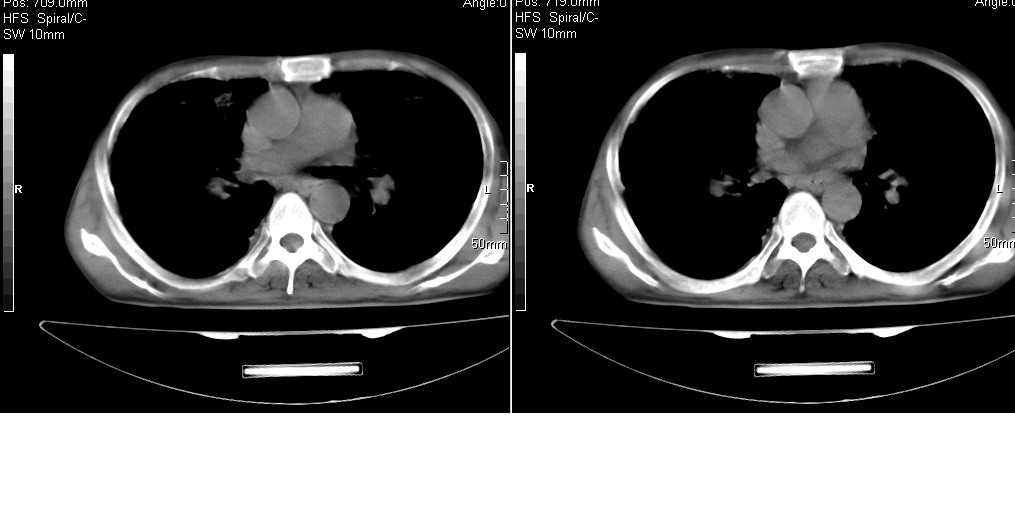

以下是引用光线在2008-5-6 18:36:00的发言:[br]双肺结核(左上肺空洞形成)、间质性改变合并感染,右肺大泡;右侧胸膜增厚。

以下是引用zsl6918在2008-5-7 1:54:00的发言:[br]首先肺泡蛋白质沉着症,其次考虑机遇性感染。